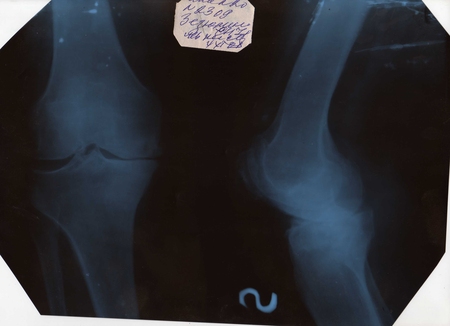

Помогите обработать фотоМне в понедельник презентацию показывать на конференции, а научный руководитель забраковал отсканированные рентгеновские снимки, сказал темно и надо осветлить в фотошопе, а У МЕНЯ ЕГО И НЕТ .....И НЕ РАЗБИРАЮСЬ В НЕМ!!!!!!!!!!!!!!!

Это остеоартроз???

По боковому снимку - совсем гибло!

Да. Анют, да тм уже последняя стадия)))) Это я преентацию для студентов делала. Буду защищаться по терапии, тема коморбидная патология артериальная гипертензия и остеоартроз, но в будущем не исключаю и ревматолога)))

а вроде как и целые кости,не вижу патологии...если не секрет-на какую тему презентация?

Остеоартроз))))))) Это уже запущенная стадия, сустав практически обездвижен

Хм...недавно повредила мениск(на велике гоняла)))),делали снимок-один в один....и суставная щель такая же и вообще...боковая проекция только может чуть отличается....приятно пошевелить декретными мозгами)))))